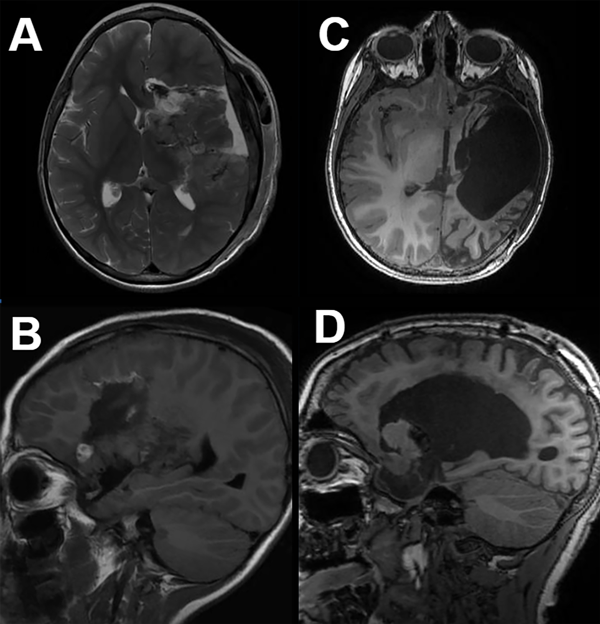

Figura 4. Imágenes de RM axial (superior) y sagital (inferior) de hemisferotomia funcional (A y B) y hemisferotomía lateral modificada (C y D). A y B: HF: se utiliza una ventana perisilviana transcortical para exponer el ventrículo lateral, y a través de esta abertura se realiza una callosotomía transventricular parasagital del cuerpo. El resto de la corteza frontal y posterior está desconectado del tálamo ipsilateral, pero se conservan las estructuras más profundas y la ACM. La craneotomía necesaria se extiende hasta la sutura sagital de la línea media. C y D: la HPI modificada extrae un bloque de tejido que incluye el opérculo frontotemporoparietal y las estructuras profundas subyacentes. La corteza frontal y posterior restante está desconectada del tálamo ipsilateral y del hemisferio cerebral contralateral.